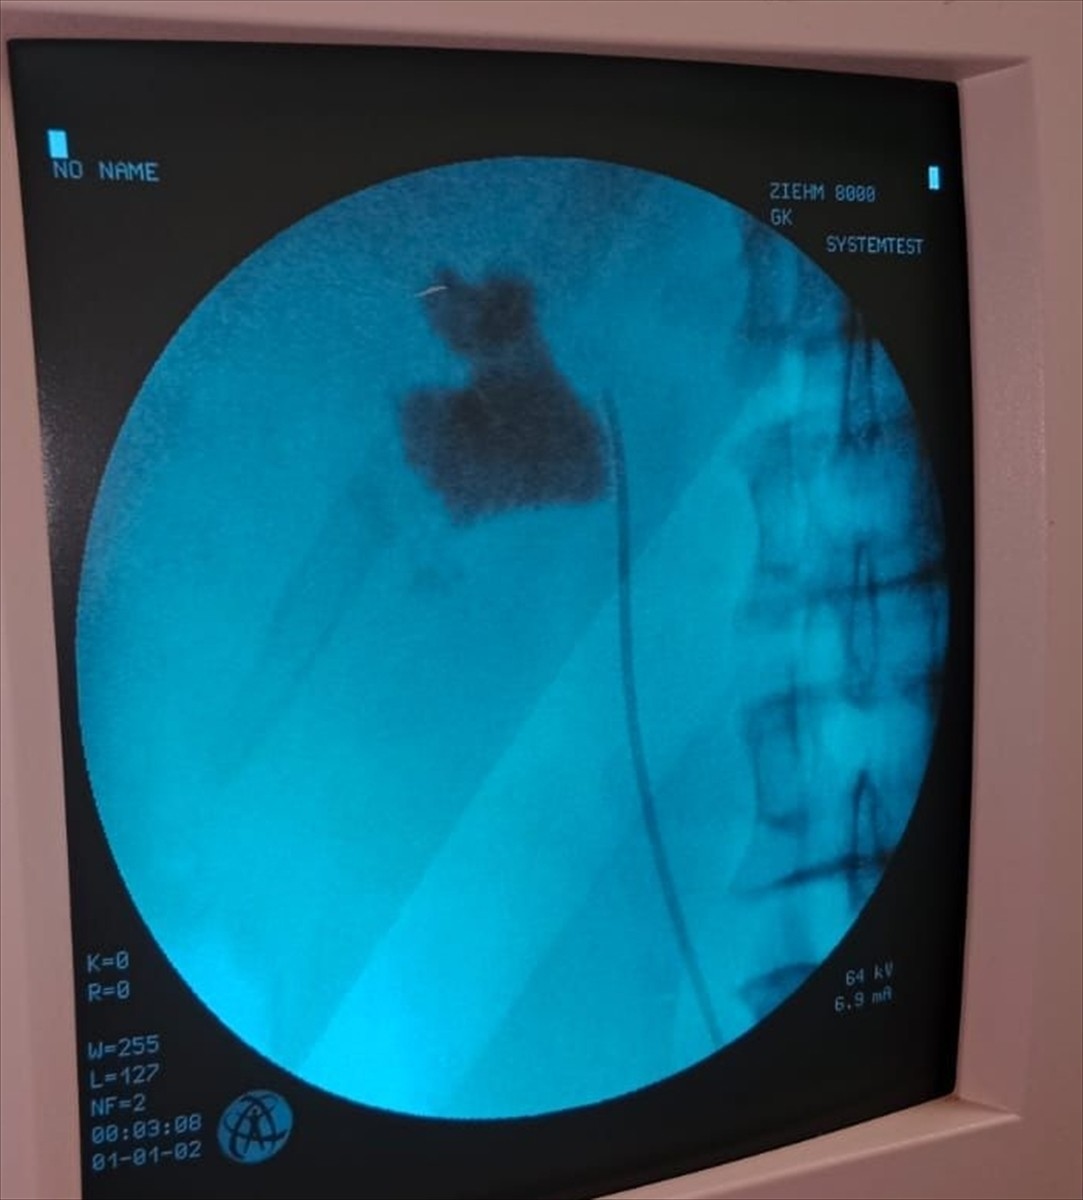

Hastaneye başvuran İlhan Çakır'ın yapılan kontrolleri sonucunda sol böbreğinde 6 santimetrelik bir taş tespit edildi. Üroloji Kliniği'nden Uzm. Dr. Talip Göktaş ve ekibi, taşın başarılı bir şekilde çıkarılması için kapalı ameliyat yöntemini seçti.

Ameliyat sonrası kısa sürede normal hayata dönen Çakır, operasyonu gerçekleştiren Dr. Göktaş ve ekibine teşekkürlerini iletti. Uzm. Dr. Göktaş, gerçekleştirdikleri ameliyat hakkında yaptığı açıklamada, "Kapalı böbrek taşı yöntemi PNL ile işlemi gerçekleştirdik. Hastamız bir gün sonra taburcu edildi. Bu yöntemle hastalarımız, açık ameliyatlara göre daha hızlı iyileşiyor ve daha konforlu bir süreç geçiriyor," dedi.

Kırşehir'de bir hastanın böbreğindeki 6 santimetrelik taş, kapalı ameliyatla alındı. Kırşehir Eğitim ve Araştırma Hastanesi Üroloji Kliniğinden Uzm. Dr. Talip Göktaş (ortada) ve ekibi tarafından kapalı ameliyatla İlhan Çakır'ın (solda) böbreğindeki taş başarılı bir şekilde çıkarıldı.